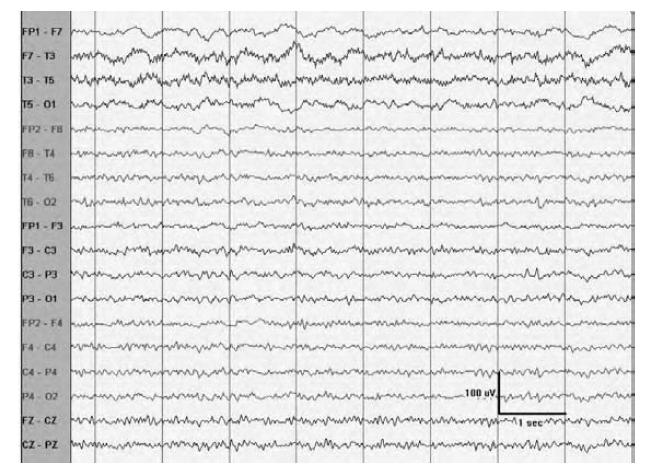

WHAT PATTERN IS SHOWN?

Generalized monomorphic 5 to 6-Hz theta frequencies

obtained during syncope in a patient undergoing head-up tilt table testing for

neurocardiogenic syncop